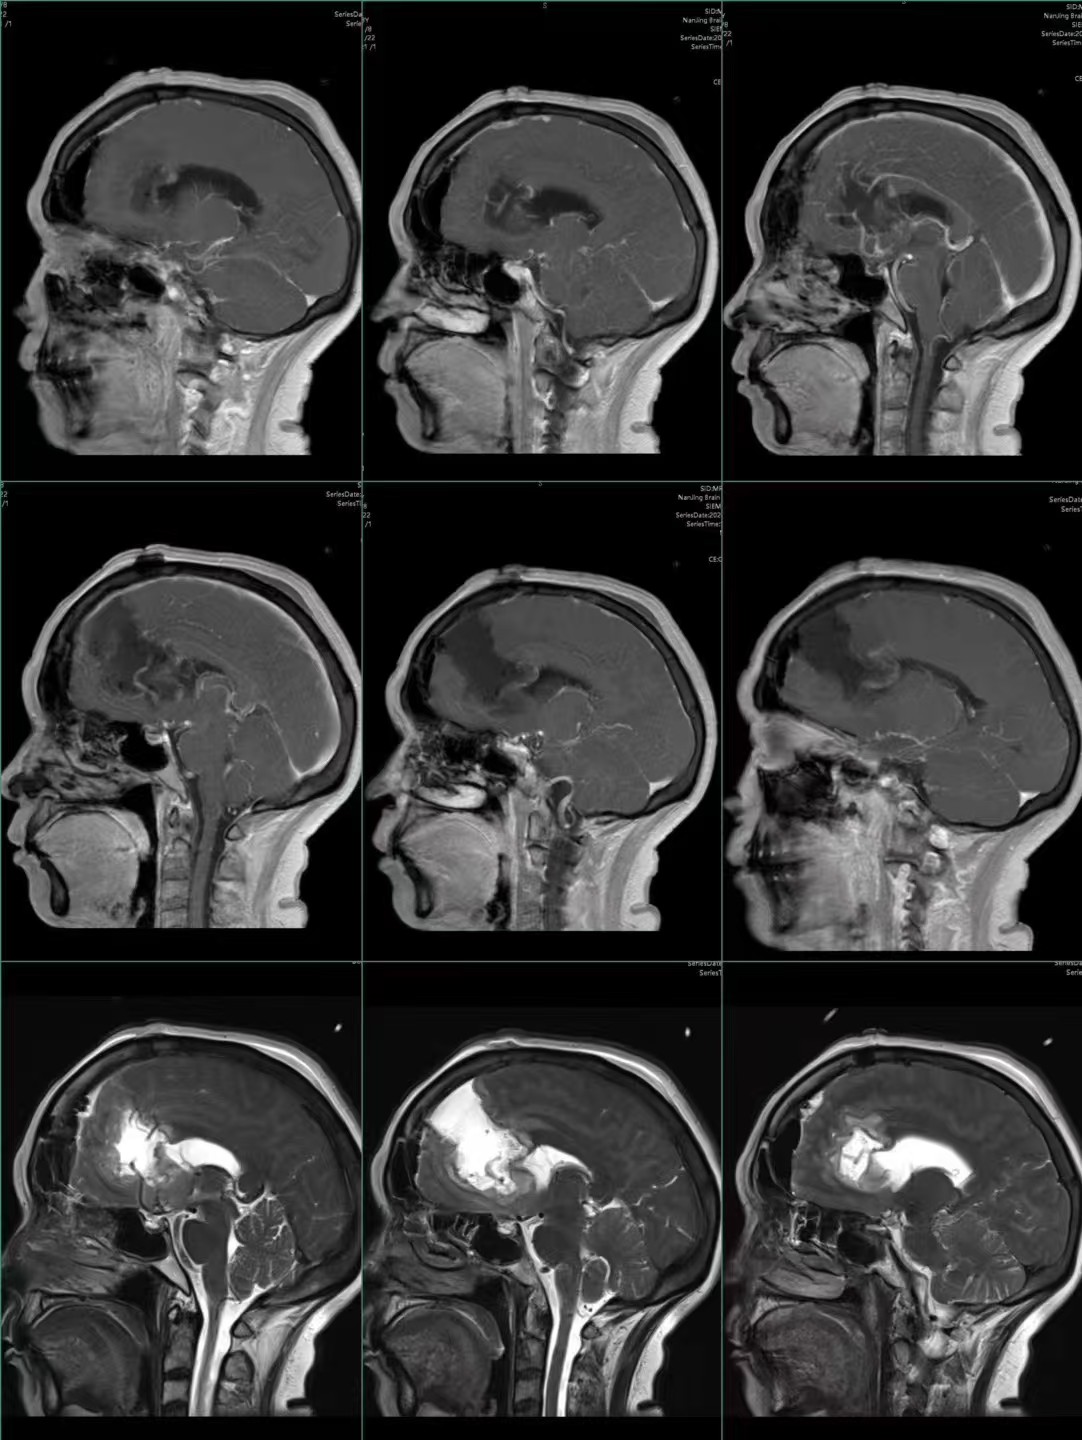

巨大蝴蝶型胶质母细胞瘤(Butterfly glioblastomas)切除术

患者,女性,58岁,因“反应迟钝、记忆力下降1月,加重伴头痛、恶心、呕吐1周”入院。

术后第二天,患者症状显著改善,认知功能明显好转

术后半月恢复正常生活

蝴蝶型高级别胶质母细胞瘤(Butterfly glioblastomas),临床相对较少见,手术风险及难度均较大,总体预后不佳。欢迎各位专家批评指正!